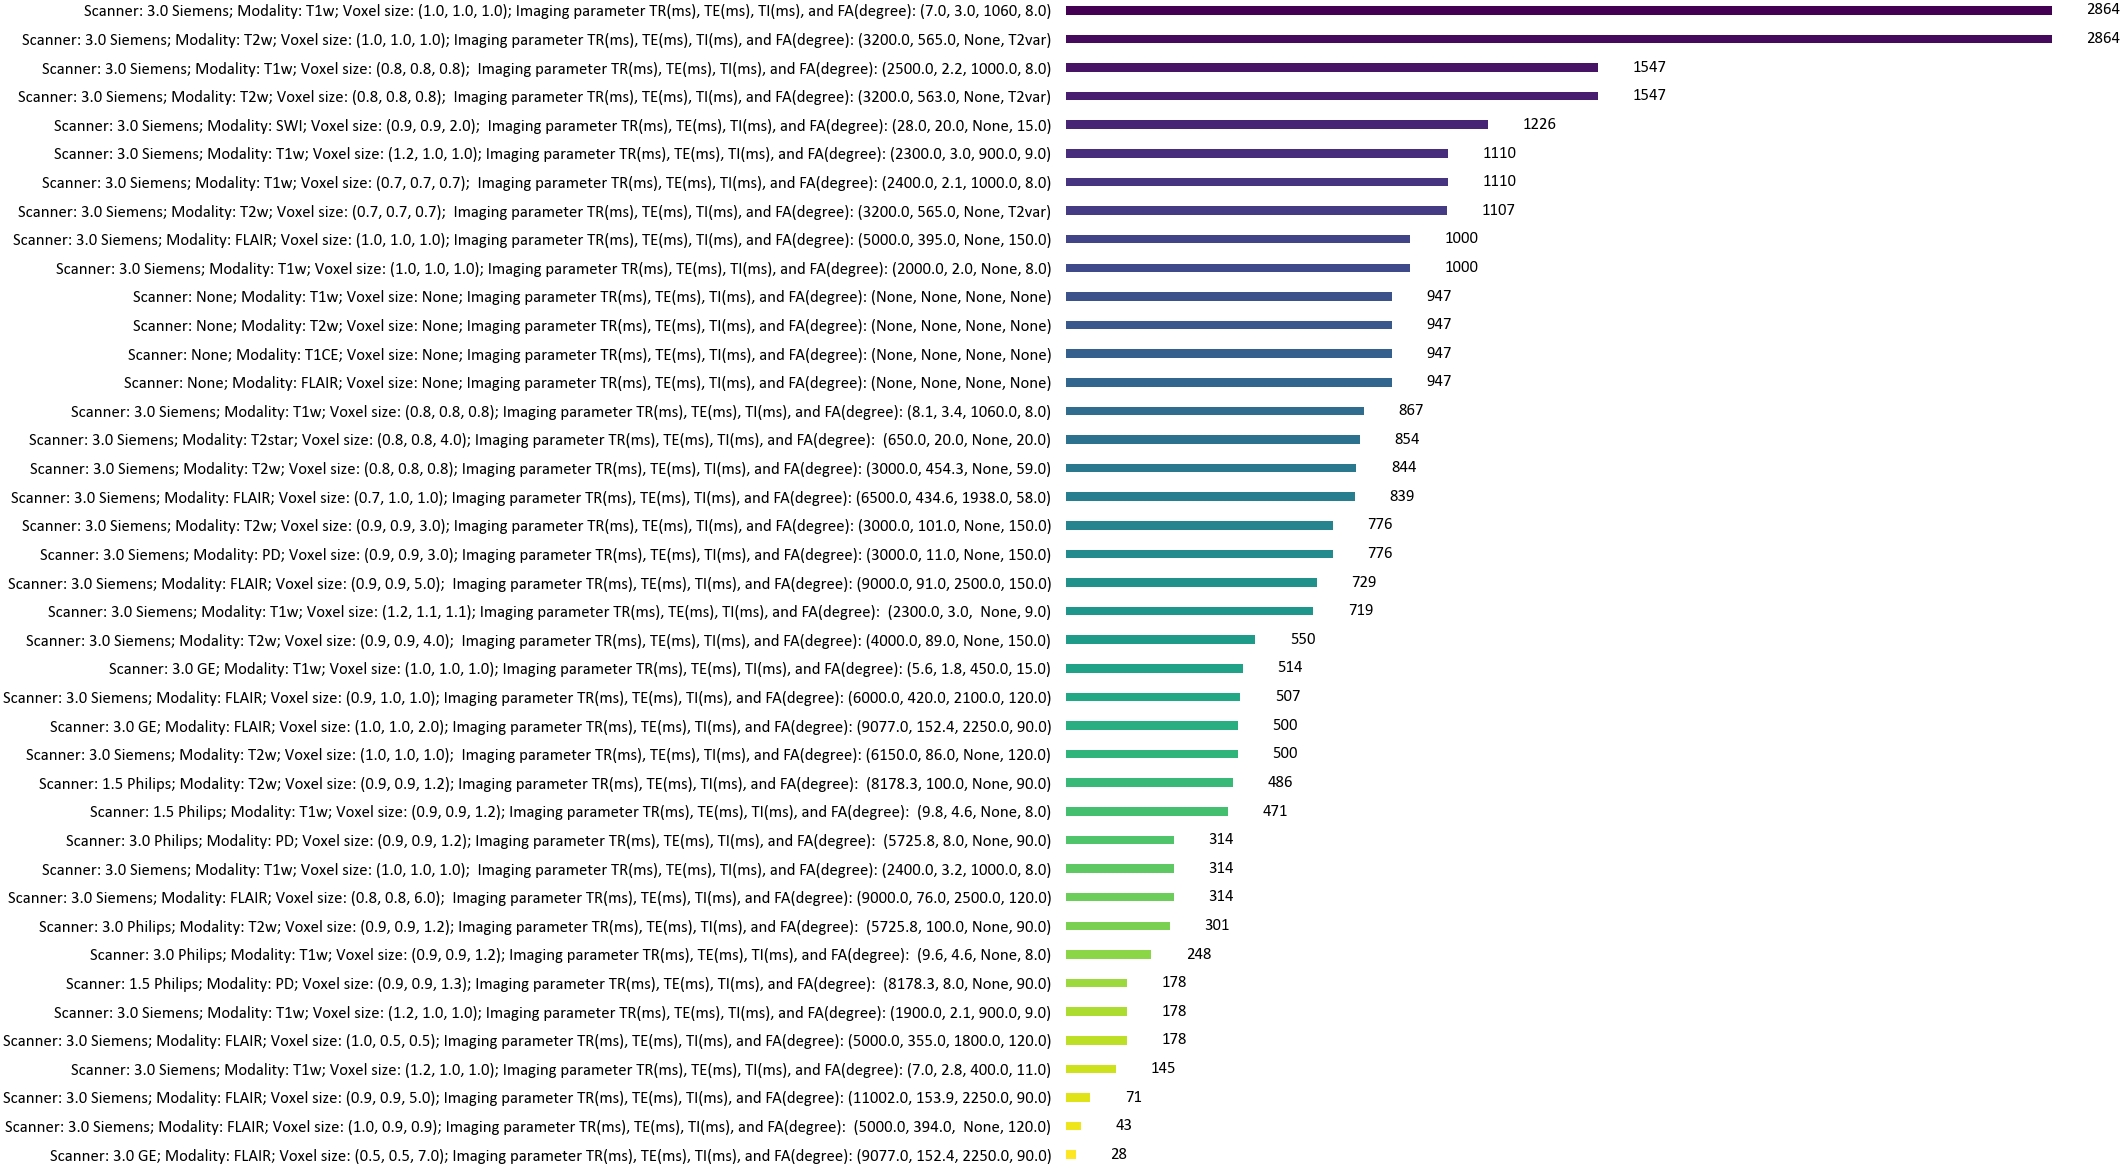

To establish a large-scale brain MRI dataset, we collected 31,407 3D scans of 12,487 individuals from diverse institutions around the world spanning ages from 2 to 100+ years old across four continents, including Open Access Series of Imaging Studies (OASIS) [33], Human Connectome Project (HCP) [34], IXI [35], Australian Imaging Biomarker and Lifestyle (AIBL) [36], Brain Tumor Segmentation (BraTS) Challenge 2021 [37], Chinese Brain Molecular and Functional Mapping (CBMFM), Adolescent Brain Cognitive Development (ABCD) [38], UK Biobank [39], Ren Ji Hospital in Shanghai, and Alzheimer’s Disease Neuroimaging Initiative (ADNI) [40], where HCP includes HCP Development (HCPD), HCP Young Adult (HCPY), HCP Aging (HCPA), and Baby Connectome Project (BCP) [41]. The most commonly used MRI sequences in clinics are included such as T1w, T2w, FLAIR, SWI, T2 star, PD, and contrast-enhanced T1w (T1CE) images. Most data used for this study were obtained from publicly available research articles. For in-house datasets CBMFM and Ren Ji Hospital data, the institutional review board approved the retrospective analysis of internal brain MR images. All internal digital data, including MR images and demographic information, were de-identified before computational analysis and model development. Patients were not directly involved or recruited for the study. Informed consent was waived for analyzing MR images retrospectively. The detailed information of each dataset is presented in Table 1, and the scanning parameters along with the corresponding amount of scanns are summarized in Extended Data Fig. 1.

To encourage the model to accommodate practical scenarios from multi-center data, the preprocessing step is reasonably simplified to a minimal extent. First, we performed co-registration for each subject and then stripped skulls for each scan. No other operations were conducted. To utilize text prompts, we collected demographic information and imaging parameters including field strength, scanner model, voxel size, TR, TE, TI, and FA of each scan from DICOM header files and official websites of datasets. These imaging parameters control the contrast and resolution of the image during the real MR scanning process.